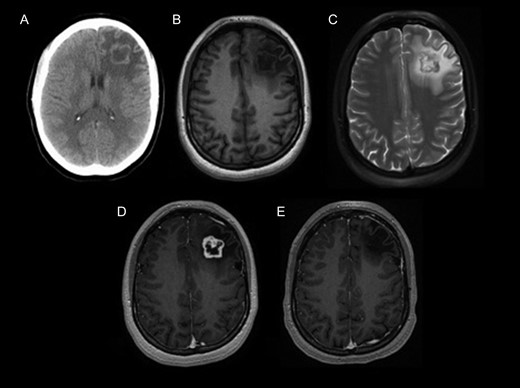

A decision for microsurgical resection was made. The patient underwent a left frontal craniotomy. Gross total resection was achieved (Fig. 1). The intraoperative interpretation was a low-grade spindle cell neoplasm consistent with low-grade astrocytoma. The patient tolerated the surgery well, with an uneventful postoperative course. She was discharged home without any complications. A 6-year post-surgery follow-up did not reveal recurrence or neurologic deficit. The pathology from paraffin embedded tissue sections revealed a well-circumscribed spindle cell neoplasm, with a biphasic pattern of hypo and hyper-cellularity, surrounded by a thin rim of gliotic cerebral parenchyma. The spindle cells contained scant cytoplasm and elongated nuclei (Fig. 2). Focally a palisaded pattern was suggested. Abundant hyalinized blood vessels were also present. These were diagnostic features of a schwannoma with no anaplastic properties.

Tumor pathology (formalin fixed paraffin embedded). (A) Tumor at low magnification reveals a biphasic pattern of a loose collagenous central zone (*) and a compact peripheral zone (+), H&E stained, original magnification ×2. (B) Trichrome stain reveals a well-circumscribed collagen-rich schwannoma (S, green color) separated from the adjacent gliotic cerebral parenchyma (C), original magnification ×10. (C) At higher magnification, this H&E stained section reveals a palisaded pattern of neoplastic spindle cell nuclei (arrows), original magnification ×20.